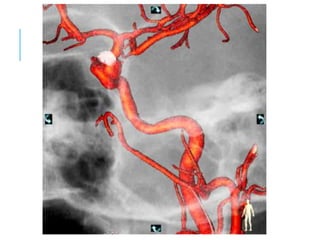

APLICACIÓN 3D

Proceso computacional mediante el cual es posible

provecho diagnóstico y terapéutico.

ANGIOGRAFÍA 3D

A esto se le llama ANGIOGRAFÍA ROTACIONAL

TRIDIMENSIONAL.

La imagen es realizada en forma instantánea.

Tiene gran utilidad en las imágenes de Aneurismas,

MAV cerebrales, como así también de ACV.

FUNCIÓN ROADMAP 3D

Este recurso permite sincronizar la imagen con el

movimiento del angiógrafo.

Para realizarlo se inyecta un poco de medio de

contraste, se obtiene la imagen 3D del vaso a

explorar. Una vez que el medio de contraste ya se fue,

el equipo es capaz de mantener la imagen del vaso

contrastado, por el que el médico podrá introducir el

catéter, guiándose por este “camino” que quedó

dibujado, como si fuera un mapa

APLICACIÓN 3D Proceso computacionalmediante el cual es posible reconstruir en forma tridemensional una imagen vascular, a partir de la adquisición radiológica de datos durante una angiografía, logrando mediante un software de aplicaciones la manipulación de tales datos para el provecho diagnóstico y terapéutico.

ANGIOGRAFÍA 3D La información,es obtenida porque durante la adquisición el equipo realiza un movimiento de 240º en 4 segundos. Formando una imagen muy similar a las entregadas por un TAC o RNM. A esto se le llama ANGIOGRAFÍA ROTACIONAL TRIDIMENSIONAL. La imagen es realizada en forma instantánea. Tiene gran utilidad en las imágenes de Aneurismas, MAV cerebrales, como así también de ACV.

FUNCIÓN ROADMAP 3D Esterecurso permite sincronizar la imagen con el movimiento del angiógrafo. Para realizarlo se inyecta un poco de medio de contraste, se obtiene la imagen 3D del vaso a explorar. Una vez que el medio de contraste ya se fue, el equipo es capaz de mantener la imagen del vaso contrastado, por el que el médico podrá introducir el catéter, guiándose por este “camino” que quedó dibujado, como si fuera un mapa